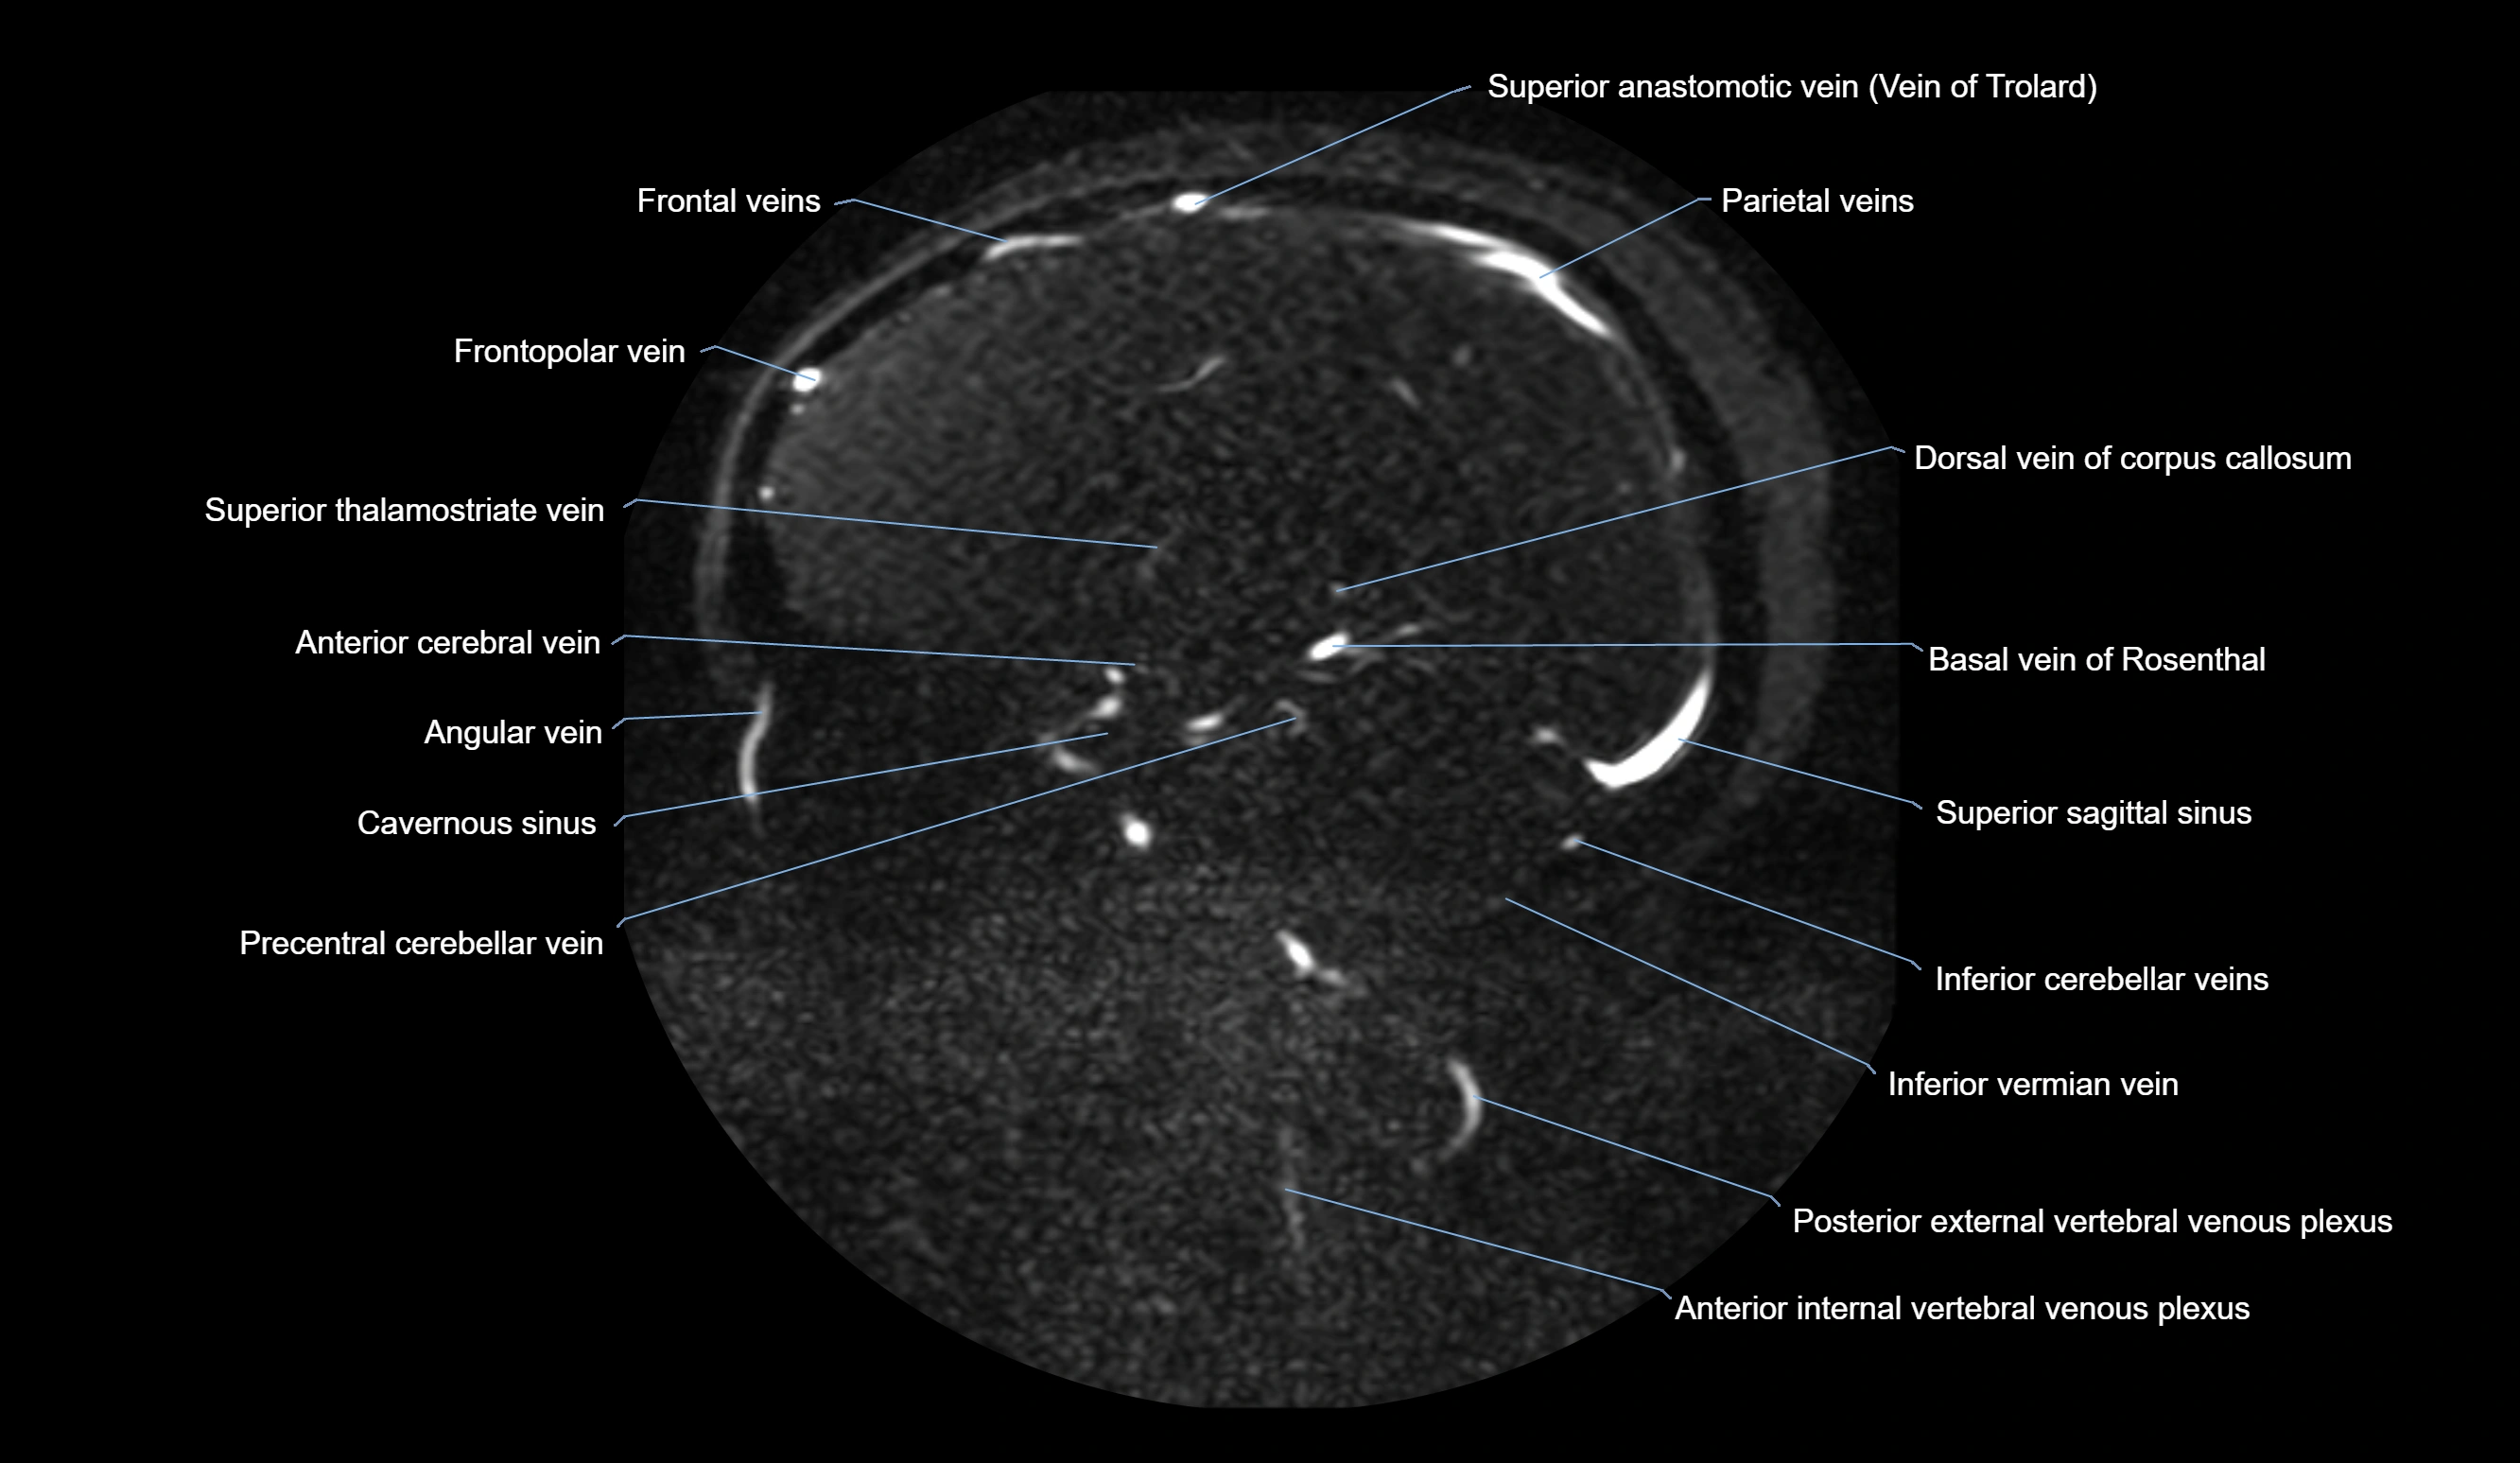

MRI Appearance

MR Venography (MRV):

• Time-of-flight (TOF) or contrast-enhanced MRV shows the angular vein as a bright enhancing venous channel

• Clearly demonstrates its continuity with the facial vein and superior ophthalmic vein

• MRV is highly useful in evaluating thrombosis, venous obstruction, or collateral venous drainage

MRI images

image